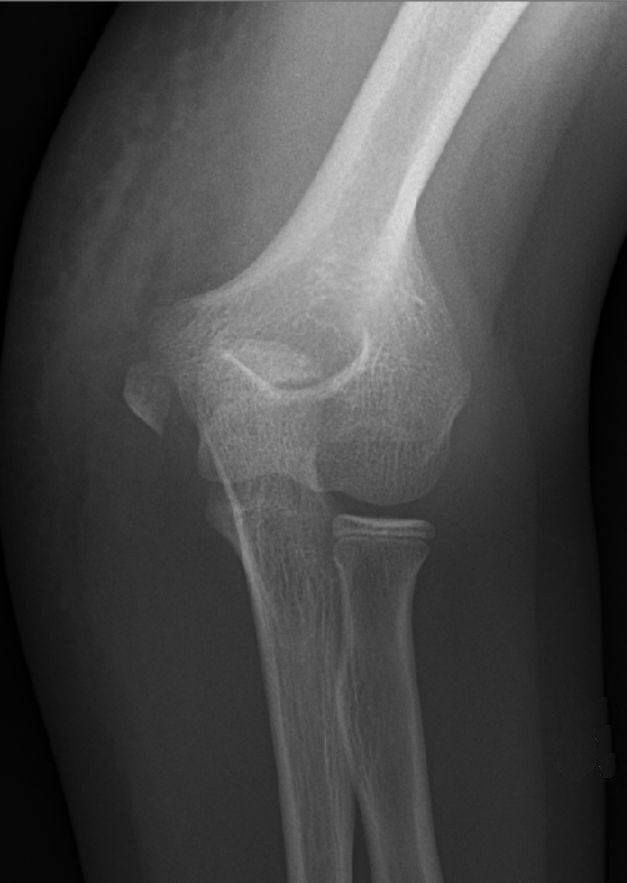

Suprakondylär humerusfraktur, Gartland 2, opererades med stiftning